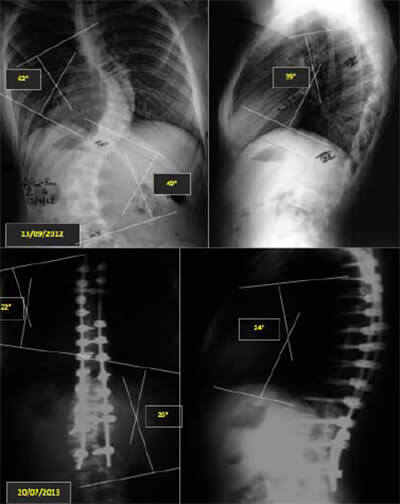

Imagen N° 1: Caso de EIA tratado mediante artrodesis instrumentada posterior con sistema de tornillos pediculares.

Imagen N° 2: Caso de EIA tratado mediante artrodesis instrumentada posterior con sistema híbrido ISOLA.